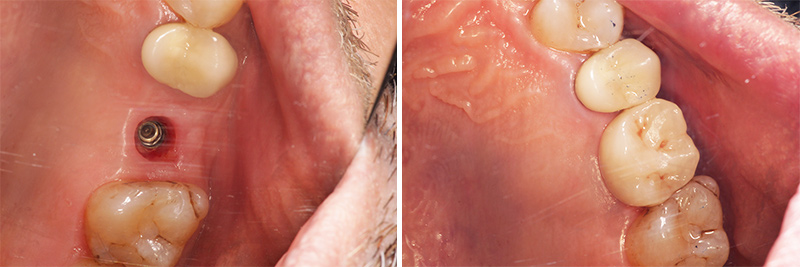

Fig. 06 : cicatrisation à 3,5 mois et mise en place de la couronne.

Fig. 06 : cicatrisation à 3,5 mois et mise en place de la couronne.

Fig. 07 : contrôle à 6 mois.